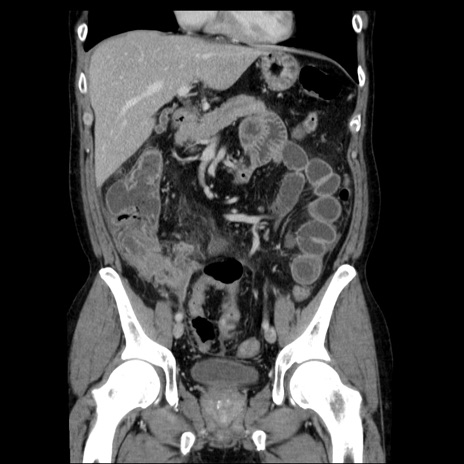

症例29(冠状断像)

【症例】40歳代男性

【現病歴】2日前から胃痛あり。徐々に周期的な激痛に変化した。本日になっても激痛があるため受診。

【身体所見】意識清明、BT 38-39℃台あり、腹部:膨満、やや硬、右下腹部に圧痛あり。

【データ】WBC 8500、CRP 23.26